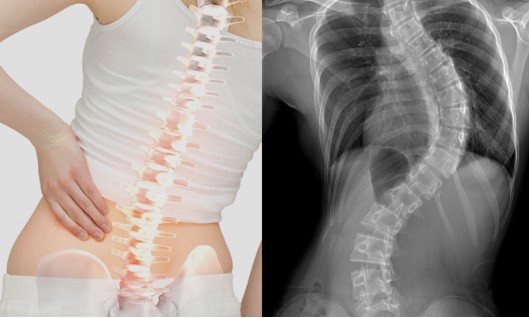

์ฒญ์†Œ๋…„์˜ 3๋ถ„์˜ 1 ์ด์ƒ์ด ๋ณ‘์ ์œผ๋กœ ํœœ ์ฒ™์ถ” ๋•Œ๋ฌธ์— ๊ณ ํ†ต์„ ๊ฒช๊ณ  ์žˆ๋Š” ๊ฒƒ์œผ๋กœ ์กฐ์‚ฌ๋˜์—ˆ๋‹ค ์ตœ๊ทผ ์„œ์šธ๋Œ€ ๋ณ‘์›์ด 3๋…„๊ฐ„ ์„œ์šธ ์‹œ๋‚ด ๋‚จ๋…€ ๊ณ ๊ต์ƒ 1,113๋ช…์„ ๋Œ€์ƒ์œผ๋กœ ์กฐ์‚ฌํ•œ ๊ฒฐ๊ณผ ์—ฌํ•™์ƒ์˜ 48%, ๋‚จํ•™์ƒ์˜ 19%๊ฐ€ ์ฒ™์ถ”์— ์ด์ƒ์ด ์žˆ๋Š” ๊ฒƒ์œผ๋กœ ๋‚˜ํƒ€๋‚ฌ๋‹ค. ๋‚จํ•™์ƒ์˜ 8%, ์—ฌํ•™์ƒ์˜ 18%๋Š” ์ฒ™์ถ”๊ฐ€ ๊ณง๊ฒŒ ์„ธ์›Œ์ง€์ง€ ์•Š๊ณ  S์žํ˜•์œผ๋กœ ํœ˜์–ด ๋ชธ์ด ํ•œ์ชฝ์œผ๋กœ ๊ธฐ์šด ๊ฒƒ์ฒ˜๋Ÿผ ๋ณด์ธ๋‹ค๋Š” ๊ฒƒ์ด๋‹ค.

์ด์— ๋Œ€ํ•ด ๋ณ‘์› ์ธก์€, ๊ณผ๋‹คํ•œ ํ•™์Šต์‹œ๊ฐ„, ์ฒด๊ฒฉ์— ๋งž์ง€ ์•Š๋Š” ์ฑ…๊ฑธ์ƒ, ๋ฌด๊ฑฐ์šด ์ฑ…๊ฐ€๋ฐฉ, ๋น„๋งŒ, ์šด๋™๋ถ€์กฑ, ์ž…์‹œ๋กœ ์ธํ•œ ์ŠคํŠธ๋ ˆ์Šค ๋“ฑ์„ ์›์ธ์œผ๋กœ ๊ผฝ์•˜์œผ๋ฉฐ ์ฒ™์ถ”๊ฐ€ ํœ˜๋ฉด ํ”ผ๋กœ๊ฐ€ ๋นจ๋ฆฌ ์™€ ํ•™์Šต ์žฅ์• ๊ฐ€ ์œ ๋ฐœ๋˜๊ณ  ์š”ํ†ต๊ณผ ๋””์Šคํฌ ๋“ฑ์ด ์ƒ๊ธฐ๊ธฐ ์‰ฝ๋‹ค๊ณ  ๊ฒฝ๊ณ ํ–ˆ๋‹ค

์ „๋ฌธ๊ฐ€๋“ค์€ ์ฒ™์ถ”๊ฐ€ ํœ˜์–ด ์ƒ๊ธฐ๋Š” ํ—ˆ๋ฆฌ ํ†ต์ฆ์„ ์ค„์ด๋ ค๋ฉด ์ฟ ์…˜ ์žˆ๋Š” ์‹ ๋ฐœ๊ณผ ์ฒดํ˜•์— ๋งž๋Š” ์ฑ…๊ฑธ์ƒ์„ ์‚ฌ์šฉํ•˜๋ฉด์„œ, ์ฒด์ค‘์กฐ์ ˆ๊ณผ ์ฒ™์ถ” ๊ฐ•ํ™” ์šด๋™์„ ํ•ด์•ผ ํ•œ๋‹ค๊ณ  ์กฐ์–ธํ•˜๊ณ  ์žˆ๋‹ค.ํ•˜์ง€๋งŒ ๋˜ํ•œ ์ฒ™์ถ”์˜ ํœœ ์ •๋„๊ฐ€ ์‹ฌํ•  ๊ฒฝ์šฐ ๋ณ‘์›์„ ์ฐพ์•„ ์ง„๋ฃŒ๋ฅผ ๋ฐ›๊ณ  ๋”ฐ๋ผ ์น˜๋ฃŒ ๋ณด์กฐ ๊ธฐ๊ตฌ๋ฅผ ์‚ฌ์šฉํ•  ๊ฒƒ์„ ๊ถŒํ•˜๊ณ  ์žˆ๋‹ค.